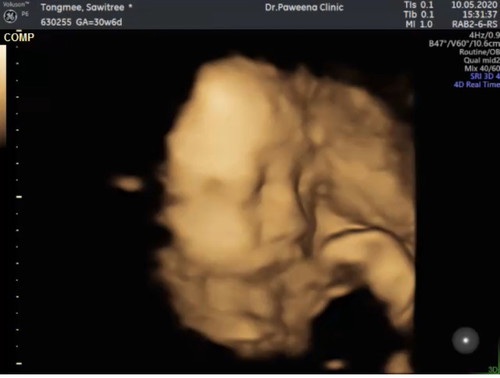

แม่ทีม กค น้ำหนักน้องเท่าไรแล้วคะ บ้านนี้พุ่งไป1800 แล้ว เพศชายคะ แอบไปดูตัวมาเมือวาน แม่ๆเอารูปมาอวดกันหน่อยคร้าา???

แก้มตุ่ยเลยครับ 😍

หมอบ่นแล้วน้องตัวใหญ่คร้าาา😂😂